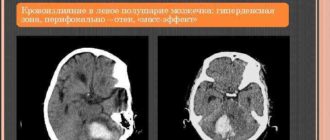

Микрокровоизлияния в левой гемисфере мозжечка

Невропатолог

Инсульт мозжечка (мозжечковый инсульт): причины, симптомы, восстановление, прогноз © А. Олеся Валерьевна, к.м.н., практикующий